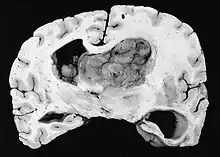

Subependymal giant cell astrocytoma (SEGA, SGCA, or SGCT) is a low-grade astrocytic brain tumor (astrocytoma) that arises within the ventricles of the brain.[1] It is most commonly associated with tuberous sclerosis complex (TSC). Although it is a low-grade tumor, its location can potentially obstruct the ventricles and lead to hydrocephalus.